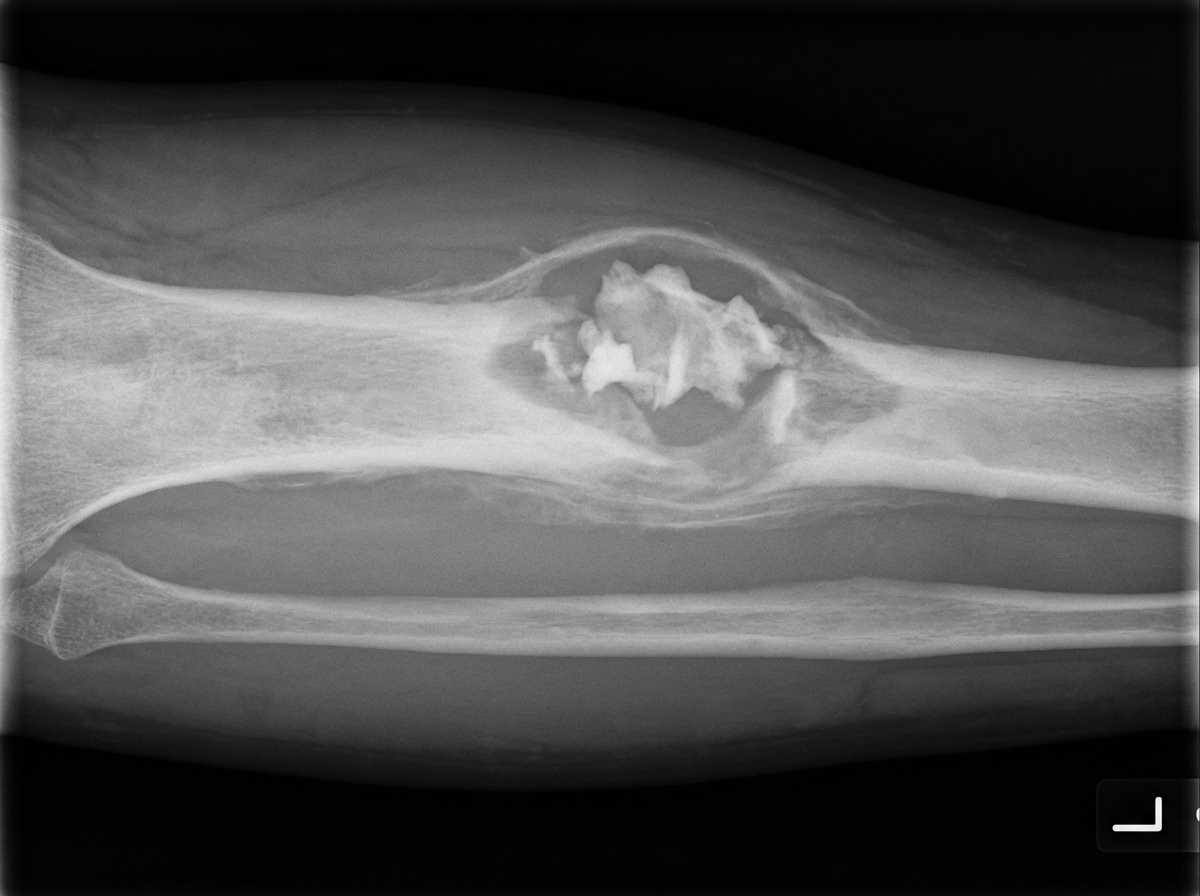

Explanation: **Explanation:** The **upper end of the tibia** (proximal tibia) is the second most common site for a **Giant Cell Tumor (GCT)**, following the distal femur. GCT is a benign but locally aggressive tumor that characteristically occurs in the **epiphysis** of long bones after the growth plate has closed (skeletal maturity, ages 20–40). Radiologically, it presents as an eccentric, "soap-bubble" lytic lesion that extends to the subchondral bone. **Why other options are incorrect:** * **Unicameral Bone Cyst (UBC):** Typically occurs in the **metaphysis** of long bones (most commonly the proximal humerus) in children and adolescents. It is a centrally located, fluid-filled cavity. * **Aneurysmal Bone Cyst (ABC):** Usually affects the metaphysis of long bones in younger patients (<20 years). While it shows a "soap-bubble" appearance, it is characterized by blood-filled spaces and fluid-fluid levels on MRI. * **Chondroblastoma:** Although it is an epiphyseal tumor, it occurs in **skeletally immature** individuals (children/adolescents) before the physis closes. The most common site is the proximal humerus (Greater Tuberosity). **High-Yield NEET-PG Pearls:** * **GCT Hallmark:** "Soap-bubble" appearance and "Double Bubble" sign on X-ray. * **Histology:** Mononuclear stromal cells (the actual neoplastic cells) and multinucleated giant cells. * **Treatment:** Extended curettage with the use of adjuvants (like liquid nitrogen or phenol) and bone grafting/cementing (Sandwich technique). * **Denosumab:** A monoclonal antibody against RANKL used for unresectable GCT.

Explanation: ### Explanation **Correct Answer: B. Chondroblastoma** **Why it is correct:** Chondroblastoma is a rare, benign cartilaginous tumor that characteristically arises in the **epiphysis** of long bones (most commonly the proximal humerus, distal femur, and proximal tibia) in skeletally immature patients. On X-ray, it appears as a well-defined lytic lesion with a thin sclerotic rim. The hallmark radiological feature is **patchy, "fluffy," or "popcorn" calcification** within the lytic area. This occurs due to the focal calcification of the chondroid matrix, often described histologically as **"Chicken-wire calcification."** **Why the other options are incorrect:** * **A. Osteosarcoma:** Typically presents with a **"Sunburst appearance"** or **"Codman’s triangle"** due to aggressive periosteal reaction. While it produces osteoid (bone), the pattern is usually dense and cloud-like rather than discrete patchy calcification. * **C. Fibrous Dysplasia:** Characterized by a **"Ground-glass appearance"** on X-ray. This is due to the replacement of normal bone with fibrous tissue and haphazardly arranged bony trabeculae, resulting in a hazy, smoky opacity. * **D. Osteoclastoma (Giant Cell Tumor):** Also occurs in the epiphysis (after growth plate closure), but it is classically described as a **"Soap-bubble appearance."** It is a purely lytic lesion and typically lacks internal calcification. **NEET-PG High-Yield Pearls:** * **Location:** Chondroblastoma is one of the few tumors found in the **Epiphysis** (Mnemonic: **C**hondroblastoma, **G**iant Cell Tumor, **E**piphyseal—"**CGE**"). * **Age:** Usually occurs in the 2nd decade (10–20 years), before the epiphyseal plate closes. * **Histology:** Look for **"Chicken-wire calcification"** (calcification surrounding individual chondroblasts). * **Treatment:** Curettage and bone grafting.